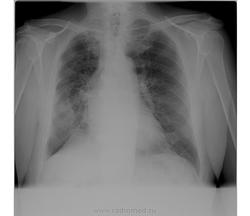

Шварта. Видно на боковом.

она же и на прямом такая обширная что ль?

Эти так называемые дела можно назвать уплотнённой междолевой плеврой.)) Это главная которая. У кардиологических, бывает, плотнеет она.